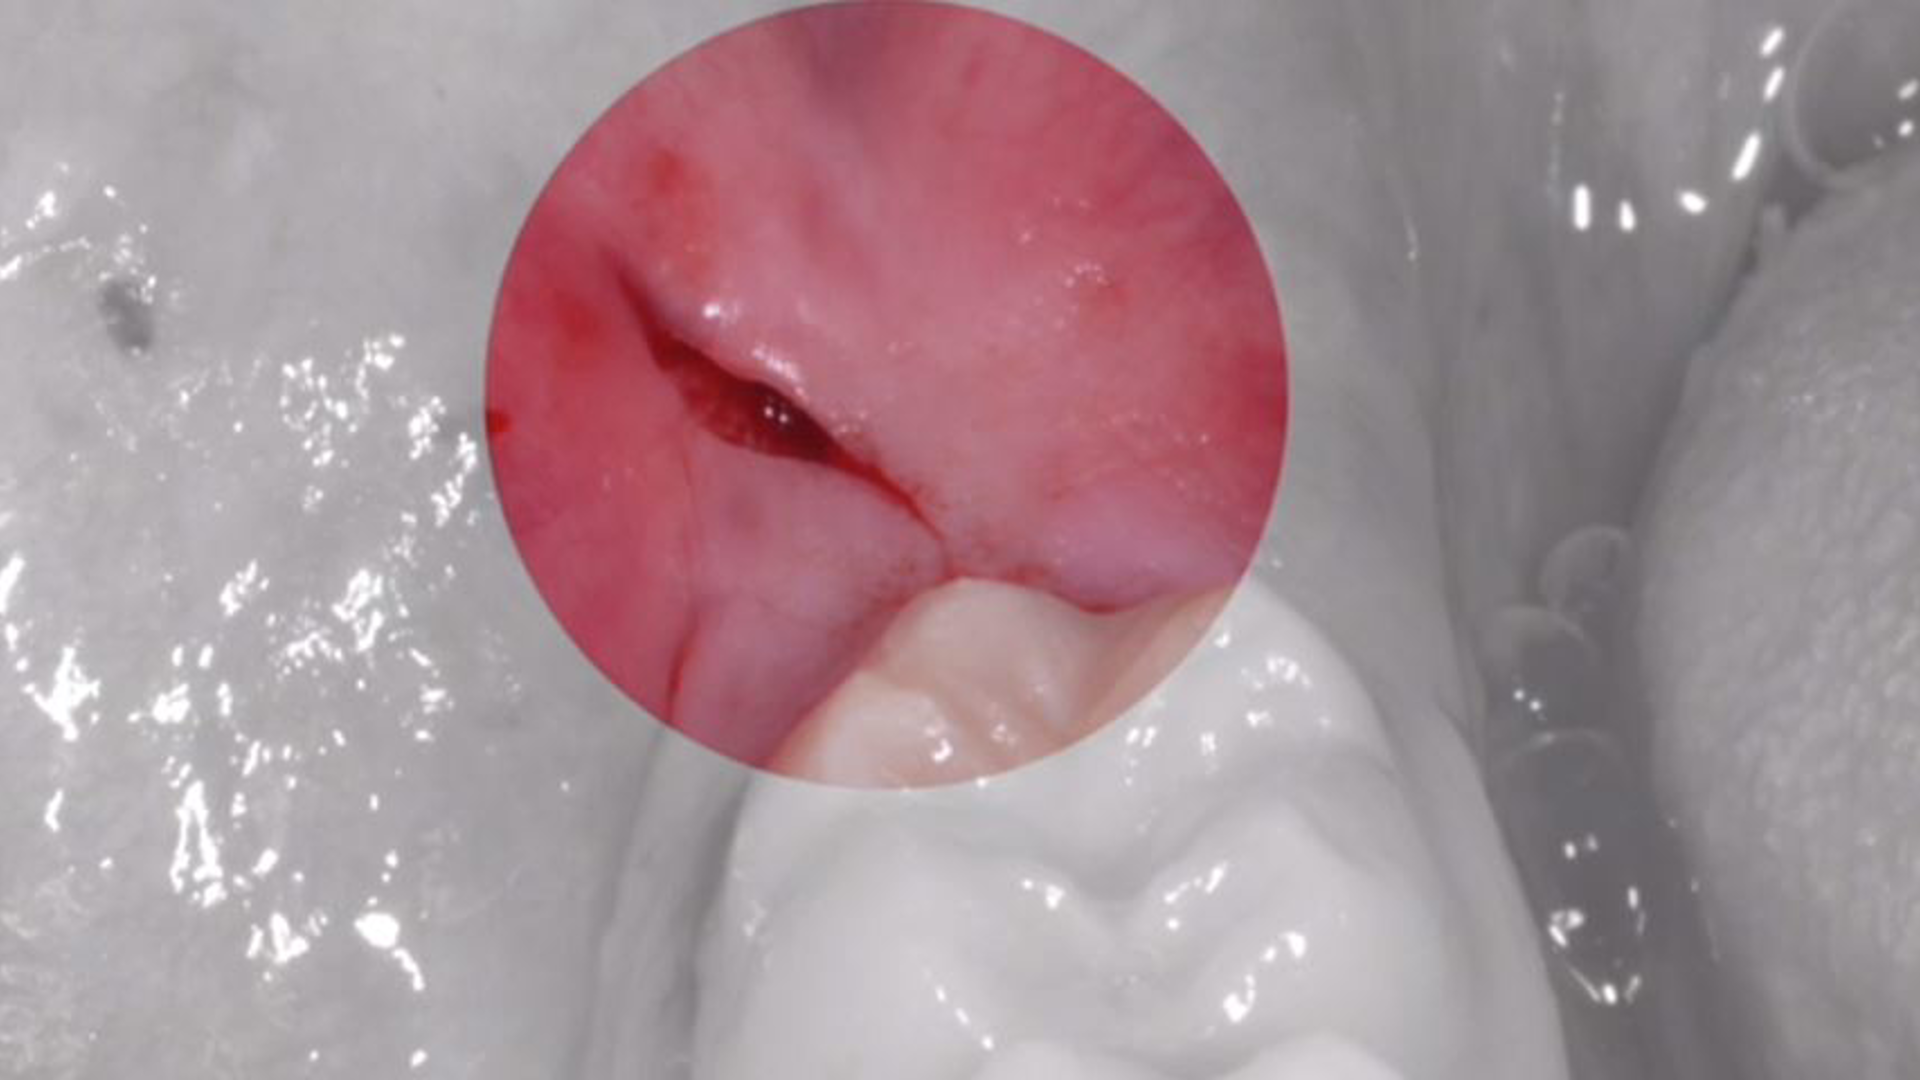

Lower right third molar extraction with deep scar tissue adhesions and fibrosis